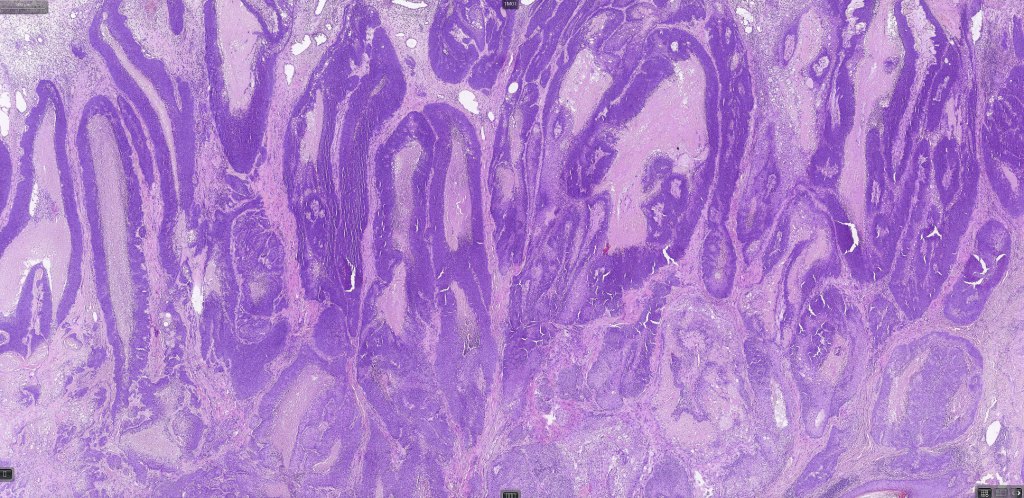

Histological features

•Well differentiated lobular growth pattern though to a poorly differentiated tumor often showing a diffuse, infiltrating border which may extend into the subcutaneous fat

•Peripheral palisading with retraction artifact and mucin deposition as seen in basal cell carcinoma is not present

•Comedo type necrosis commonly present

Sebaceous carcinoma from a patient with Muir-Torre syndrome kindly shared by Dr. Antonina Kalmykova.